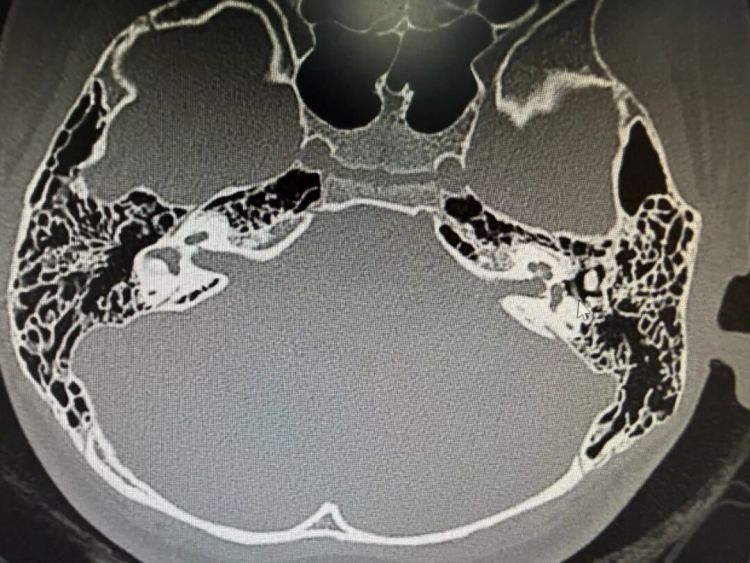

显微镜下,丁医生仔细磨除外耳道闭锁区域的骨质,一点一点开辟出新的外耳道。通道打通后,手术团队精准植入了一块全钛人工听骨,重新构建起声音传导的“桥梁”。

术后检查显示,女孩的听力得到了大幅改善,更重要的是,面神经功能完好无损,没有出现任何并发症。

术后的外耳道